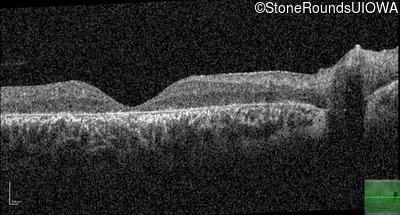

This 14 year old male began having trouble reading before the 1st grade. His parents noticed that he would not look directly at anyone.

| Disease | Gene | Allele 1 variant(s) | Allele 2 variant(s) | Inheritance mode |

|---|---|---|---|---|

| AR Stargardt Disease | ABCA4 | Ala1038Val GCC>GTC / Leu541Pro CTA>CCA | IVS36+3 del4tAAGT | AR |